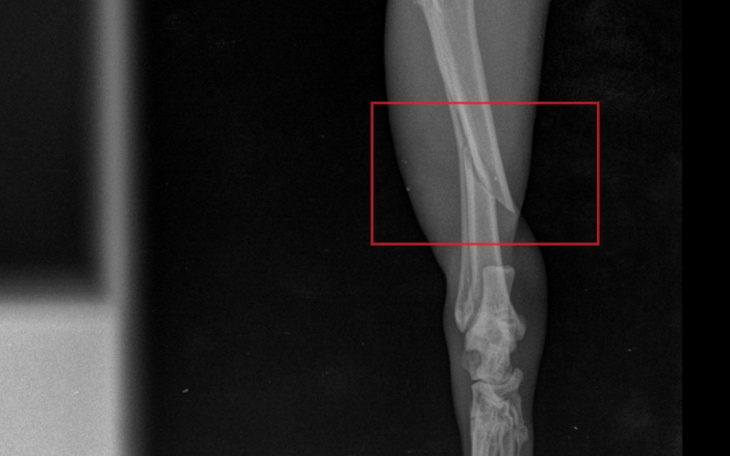

Zdjęcie RTG wykonane następnego dnia w żnińskiej lecznicy wykazało, iż złamaniu uległa kość piszczelowa tylnej łapki.

Przy okazji poddano kotka zabiegowi kastracji. W związku z tym, że złamania nie mogą czekać i każdy kolejny dzień zwłoki zmniejsza szansę na przywrócenie sprawności natychmiast skonsultowałyśmy przypadek z okolicznymi lecznicami oferującymi usługi ortopedyczne.